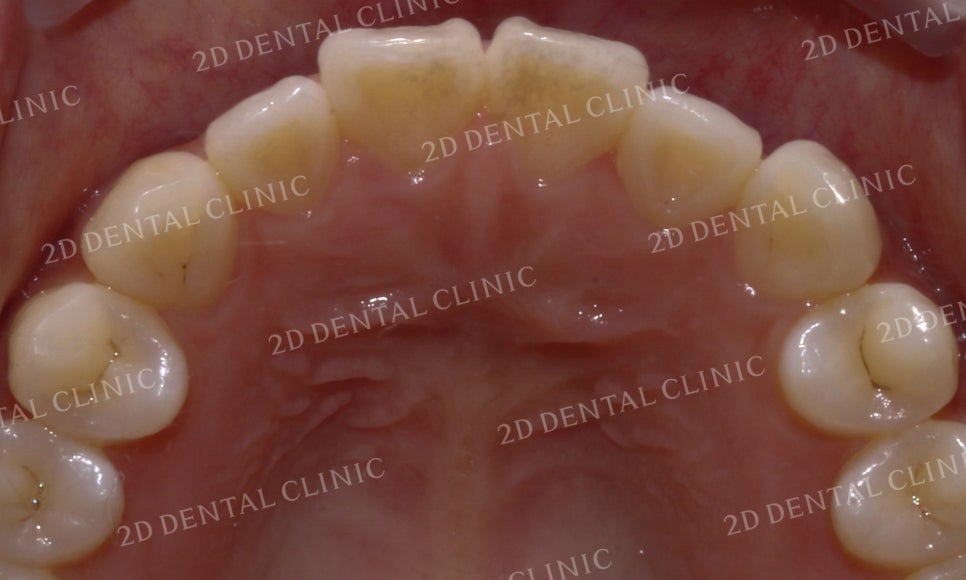

하악의 설측면에서도

전치부에서 삐뚤거리는

크라우딩이 발견되던 교정 전과 달리

교정 후 삐뚤삐뚤한 부분 없이

깔끔하게 마무리된 모습입니다.

이번 Case의 환자분은

돌출감이 심한 전치부의

치아만을 교정하시기 원하셨습니다.

따라서 구치부의 치아들은

교정을 진행하지 않았습니다.

유의하시고 포스팅을 읽어주시기 바랍니다.